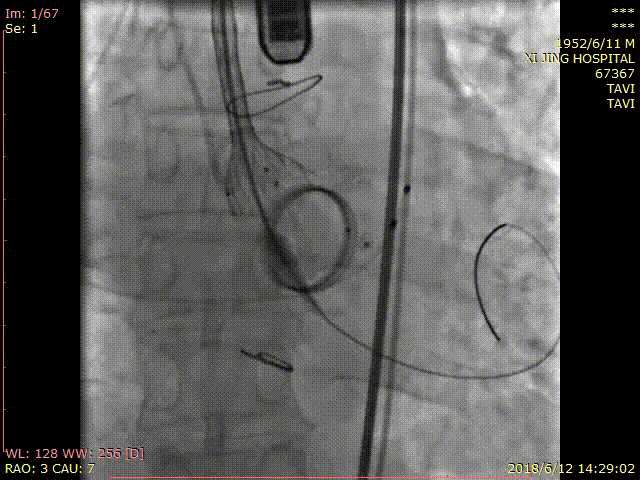

术中DSA影像:

造影检查瓣周漏